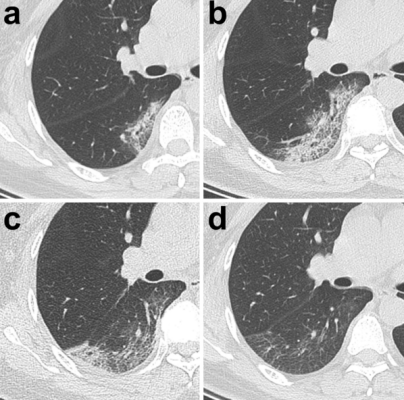

– Trong trường hợp diễn tiến xấu đi về mặt lâm sàng thì trên hình ảnh CLVT cho thấy các biểu hiện biến đổi theo hướng gia tăng mức độ trầm trọng; nghiã là thương tổn gia tăng về mặt số lượng, phân bố lan tỏa hơn, số thùy phổi bị tác động nhiều hơn [7,1011,12]; thương tổn gia tăng kích thước, lúc này vị trí thương tổn không chỉ khu trú ở ngoại vi dưới màng phổi mà còn lan dần về phía trung tâm; về mặt đậm độ thì thương tổn các loại có biểu hiện gia tăng đậm độ hơn, với loại thương tổn dạng kính đục thì tăng dần mật độ theo hướng hình thành đám mờ kiểu lát đá không đều (do dày ra của vách liên tiểu thùy và xuất hiện các vách bên trong tiểu thùy phổi) và mô phổi đặc thay thế dần diện kính đục, với loại thương tổn dạng đặc phổi thì đậm độ cũng gia tăng hơn, tạo nên hình ảnh “phổi trắng”, điều này khiến chức năng của phổi suy giảm hẳn. Một điểm đặc biệt là trong tiến triển của thương tổn của viêm phổi COVID-19 không có sự hình thành hốc hoại tử như trong các bệnh lý viêm phổi do nhiễm trùng. Các tiến triển xấu đi của thương tổn thường gặp ở nhóm bệnh nhân già, có bệnh lý nền (hình 4,5) .